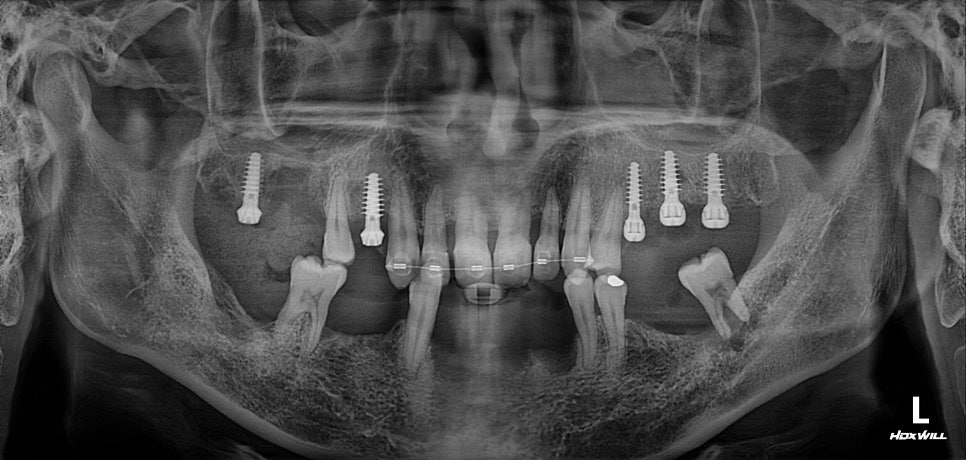

이때 "최소침습임플란트" 로

무절개로 시술하였으며

최소침습임플란트를 사용할 경우

뼈상태가 좋지 않을 때

초기고정력을 얻기 유리한 경우가 많습니다.

최소침습 매직코어 임플란트는

치료가 완료된 상태입니다.

아래쪽은 전반적으로 뼈상태가 좋지 않아서

위에 비해 치료시간이 오래 걸리긴 했지만

UV임플란트와 PDRN을 이용하여

최대한 치료기간을 단축하였습니다.